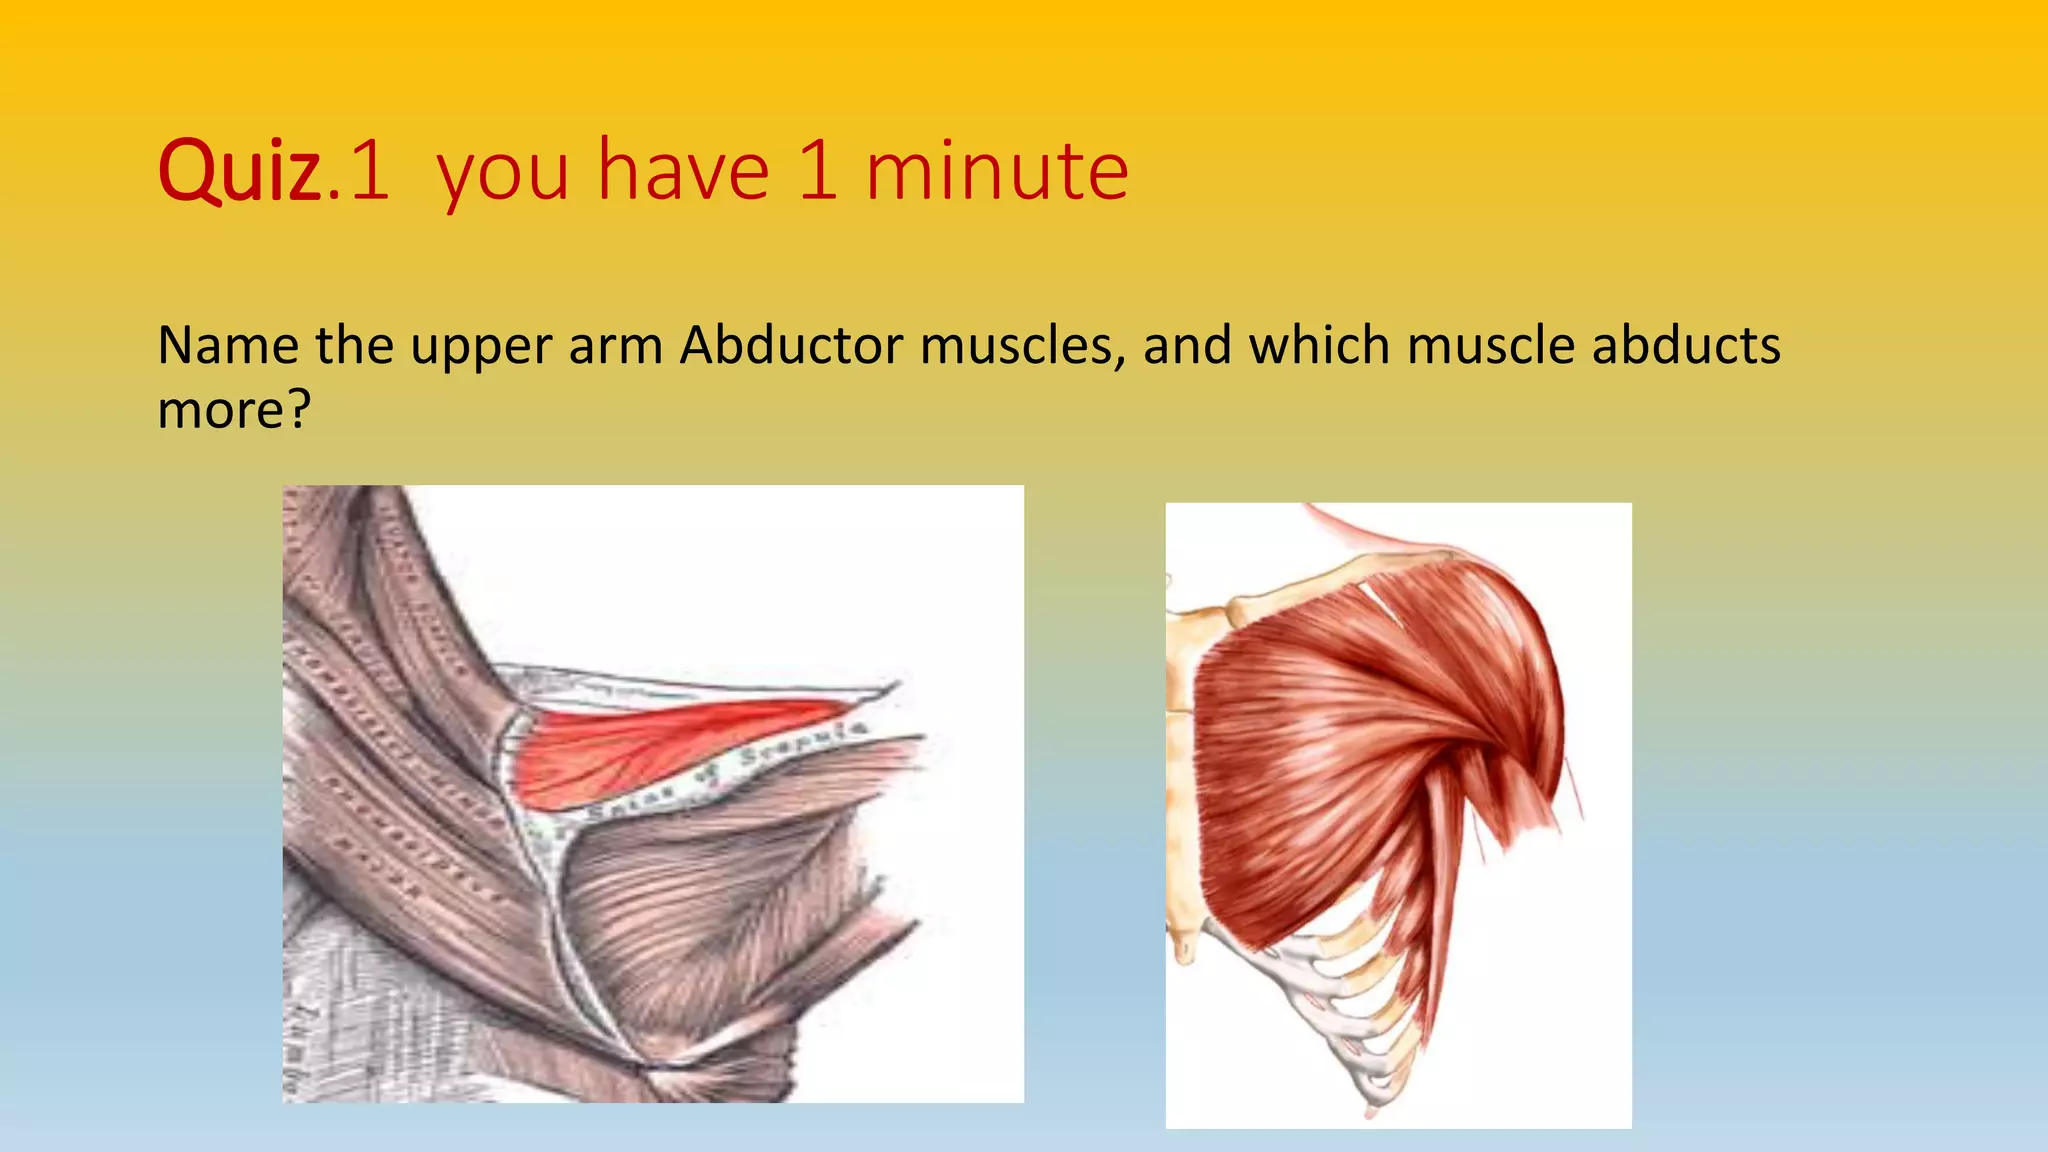

The document summarizes an anatomy revision session on the upper limb. It discusses various muscles of the upper limb including their origins, insertions, innervations and functions. Key muscles covered include the pectoralis major and minor, serratus anterior, deltoid, biceps brachii, brachialis, coracobrachialis, and triceps. It also discusses the rotator cuff muscles and muscles of the forearm including flexor carpi ulnaris and radialis. The session aims to help students identify upper limb muscles and understand their relations to nerves.